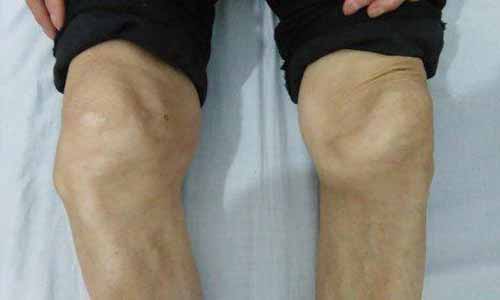

查体:肩臂抬举困难,肩前、肩后、外侧均有压痛;膝关节肿胀变形,压痛明显,走路受影响;肘关节肿胀,一压就疼,无法弯曲;双手指关节肿胀疼痛;踝关节肿胀,压痛不明显。

(图:马奶奶的膝关节肿胀变形,疼痛导致无法正常行走)